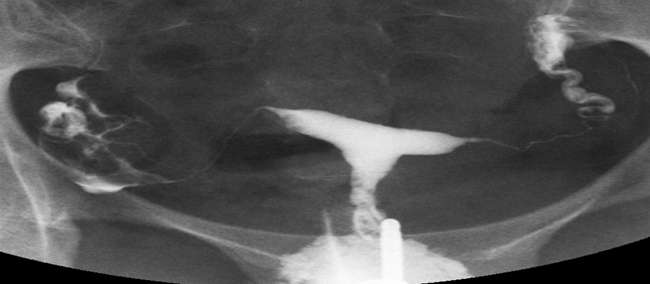

Histerosalpingografi (HSG, ilaçlı rahim ve tüp filmi veya röntgeni) kısırlık tedavisi gören hastalarda rahim içerisinin şeklen değerlendirilmesi ve tüplerin açıklığının araştırılması amacıyla yapılan bir işlemdir.

Rahim filmi çekilirken rahim içerisine ince bir kateter yardımıyla ilaç verilir. Bu ilaç sıvı bir kontrast maddedir, yani röntgen filminde görülebilecek bir sıvıdır. Bu sıvı yağ bazlı veya sıvı bazlı üretilebilmektedir. Yukarıda bahsedilen gebelik şansını arttırıcı etkinin yağ bazlı sıvılarla çekilen HSG sonrasında daha fazla arttığı gösterilmiştir bazı çalışmalarda.